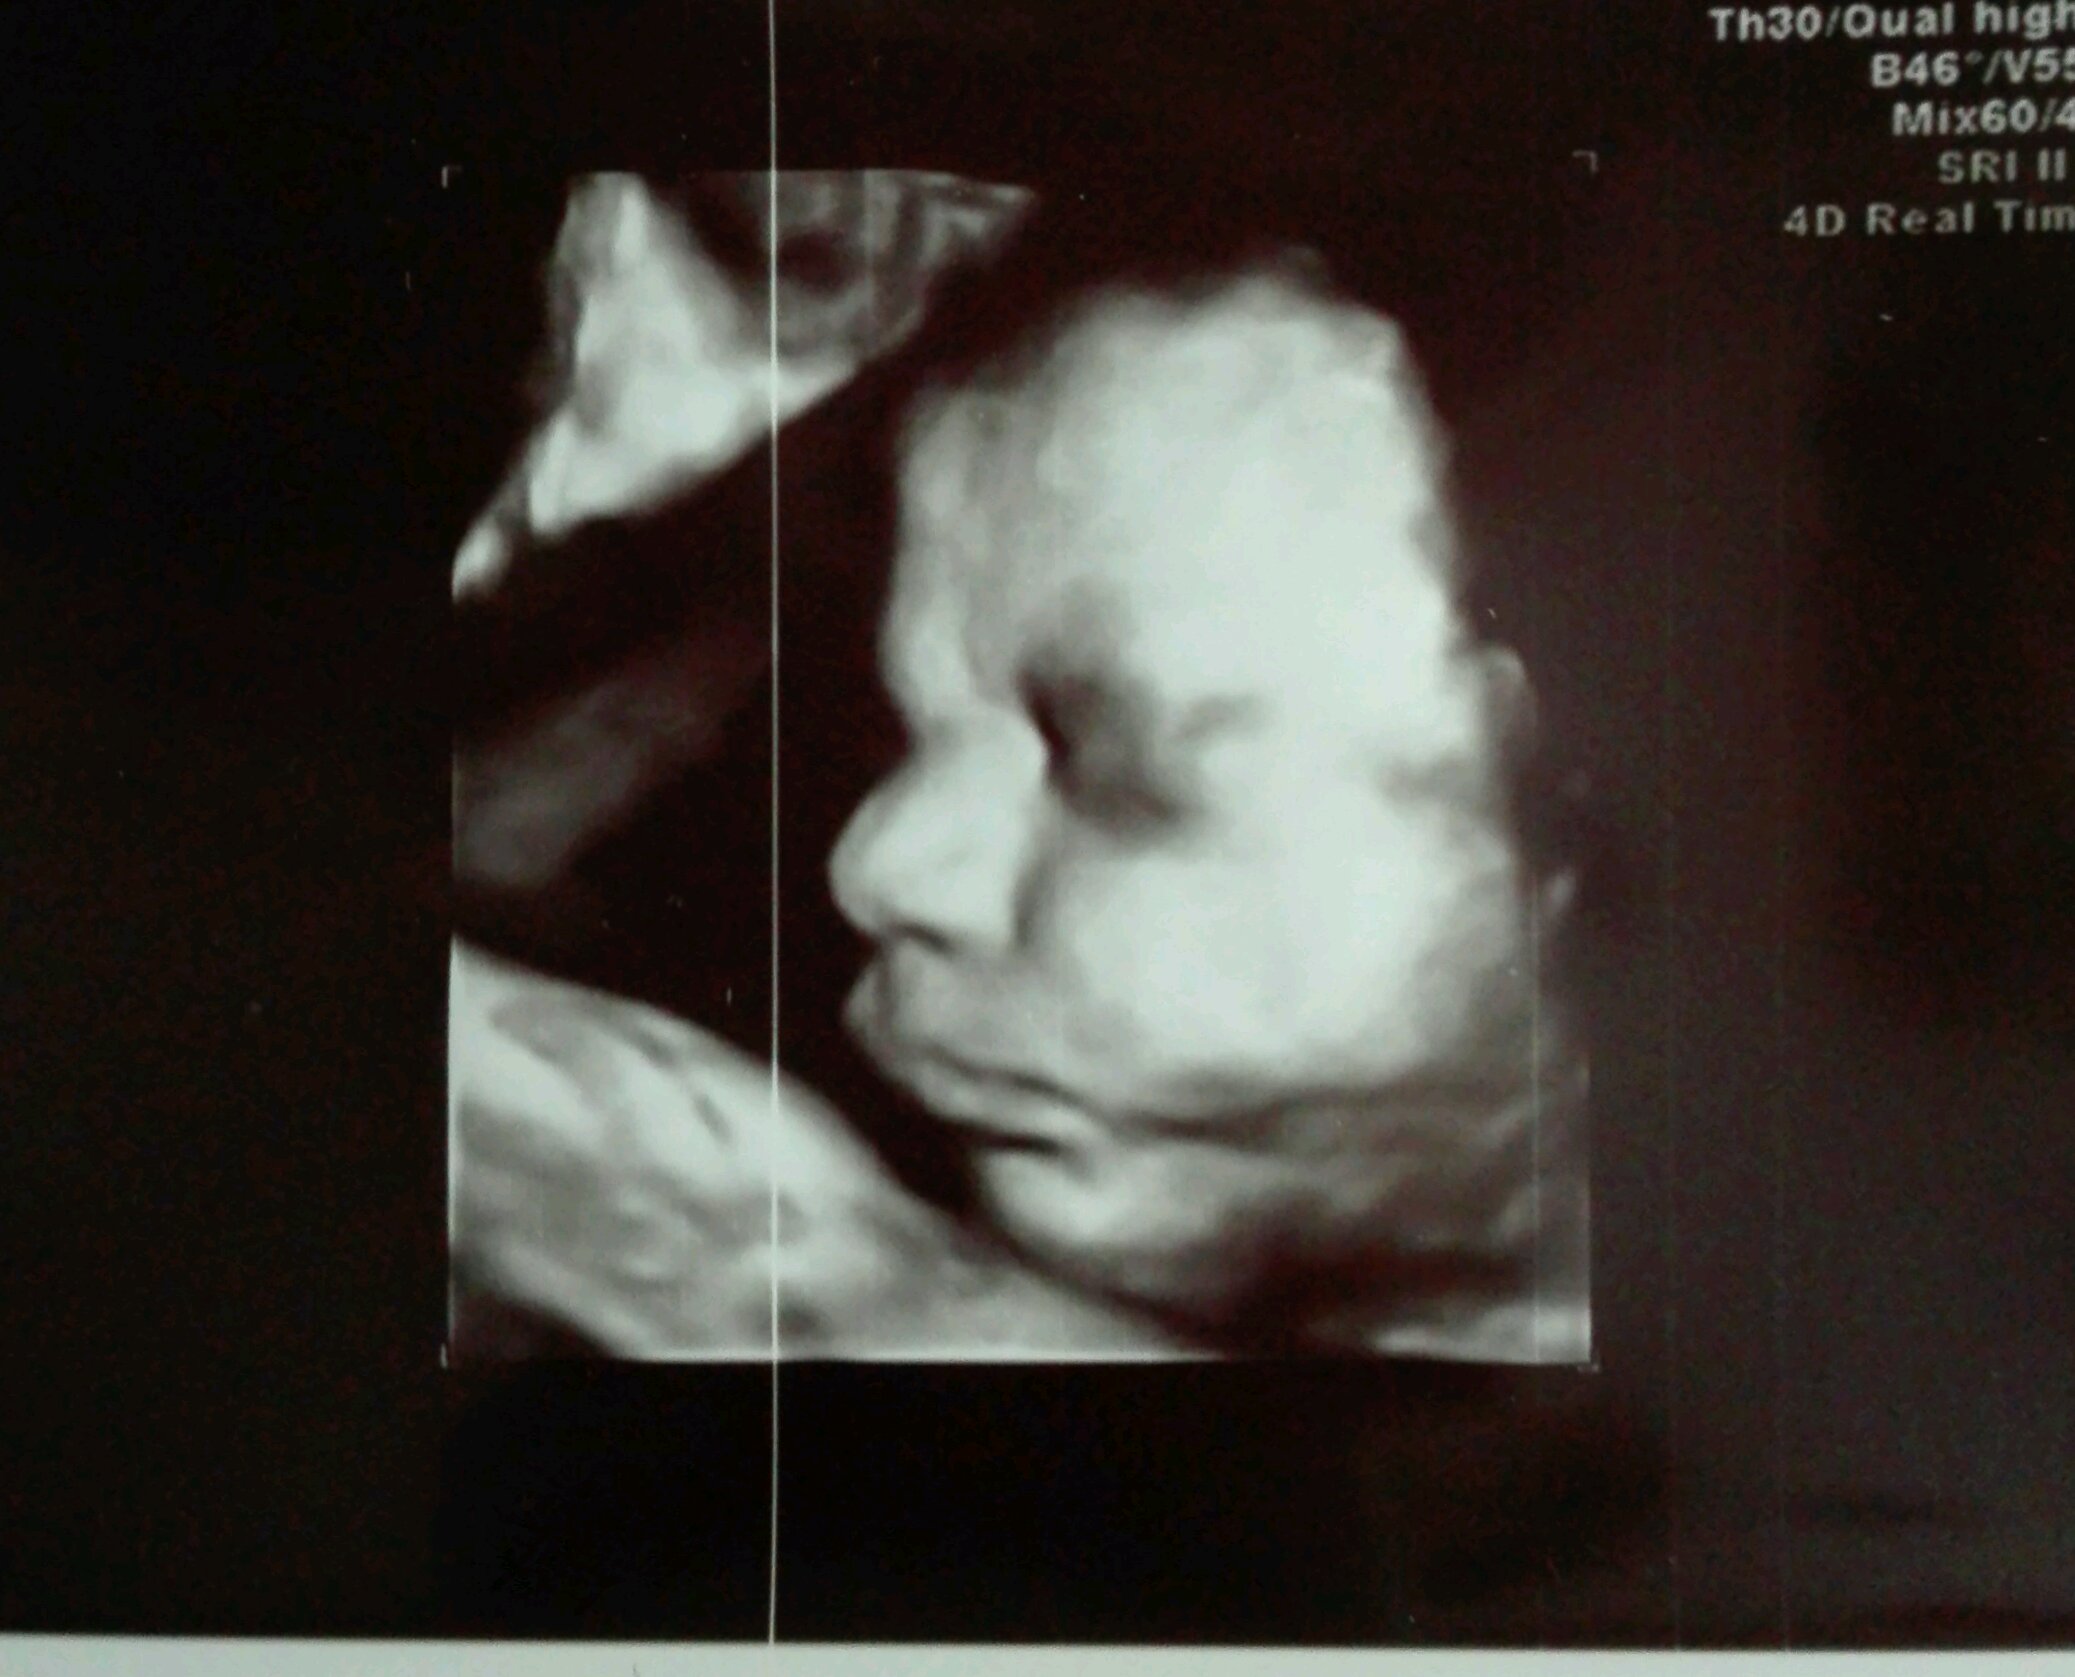

Cześć ciotki [emoji173] my dziś po usg III trymestru, u nas 31+1 [emoji7] moja malutka Lenka...w sumie nie malutka :D waży 2kg [emoji23] cały tatuś [emoji33] strasznie główka uciska mi na pęcherz i się mecze z sikami [emoji28] ogólnie wszystko super , wzorowa kluseczka [emoji7] Zobacz załącznik 868828